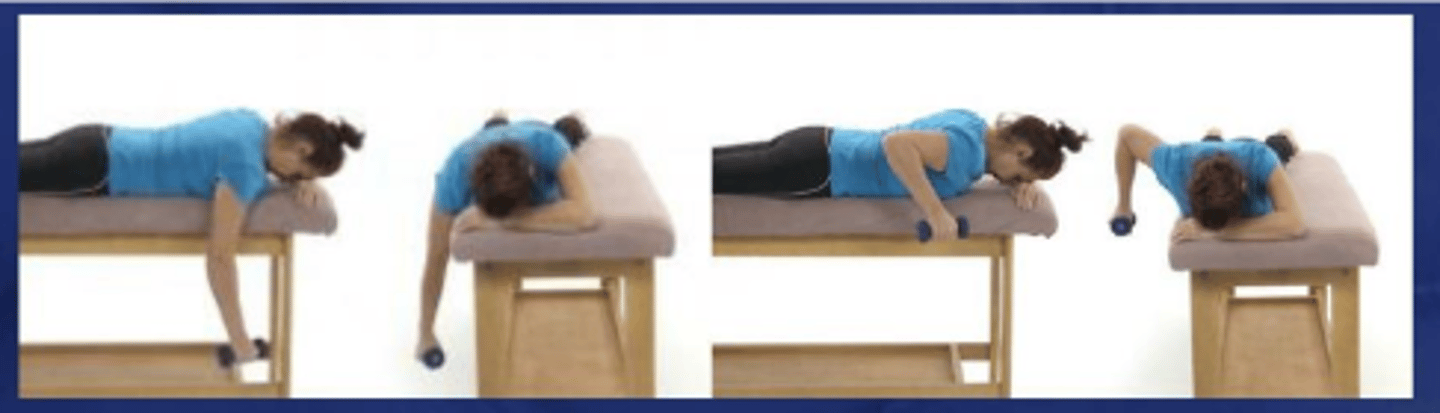

Prone rowing

What does the image show?

Prone rowing into ER

What does the image show?